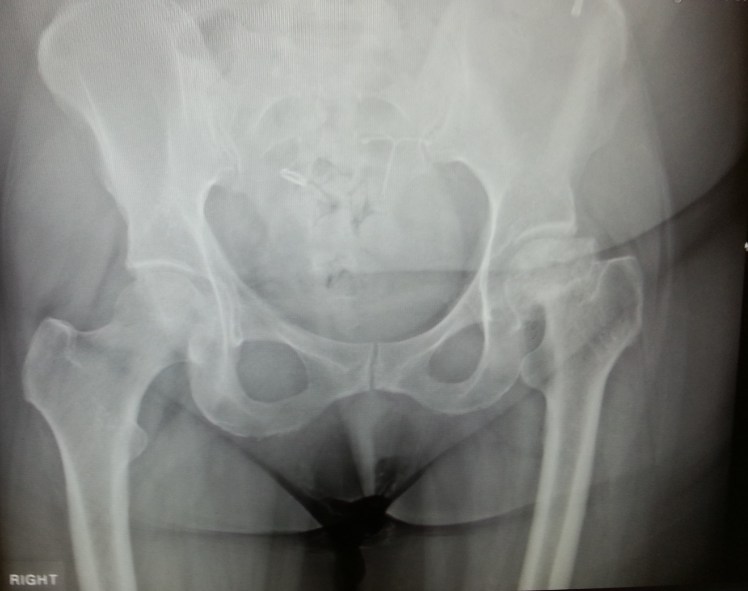

That’s what a surgeon decided three weeks ago, when I was taken into A&E sobbing with pain. Not my surgeon, of course, but a surgeon who had been told to operate on me as an emergency. I was given the requested MRI and diagnosed with avascular necrosis – no blood supply to the remains of my femur, which is now missing its neck and has a crushed ball joint. Trust me, it’s absolute carnage in there:

You’ve just looked at the x-ray that was taken on 30th November when I went to see my own consultant just a few days after being told that my weight and my chronic illnesses made me inoperable and that there was no point in my being in hospital. Nobody had told me that my consultant had been contacted, or that he’d ordered the MRI and an emergency hip replacement! Nope, sorry Mrs W, but you get to spend your life on painkillers and living between your bed and a wheelchair.